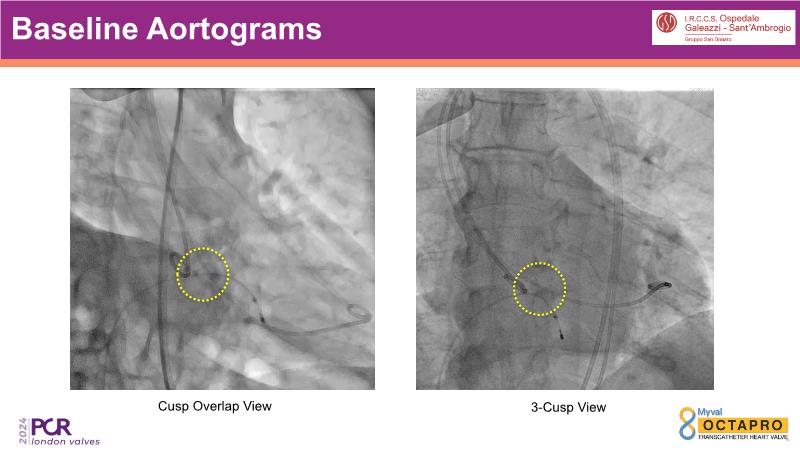

Through the presentation of several compelling cases, including an 88-year-old male with CKD, RBBB, moderate LV dysfunction, and severe aortic stenosis, a Type 1a bicuspid native AS, and an extraordinary TAVI in an 83-year-old with acute heart failure and comorbidities, this session will dive into the Myval Octapro THV. Learn about its key features, procedural impact, and potential clinical benefits. Discover the Octalign technique for predictable and precise commissural and coronary alignment, preserving coronary access. Gain insights into precise sizing, positioning, and deployment of the Myval THV series in real-world scenarios, and explore the relevance of pivotal Landmark RCTs in clinical practice.

- To know the Octalign technique which enables predictable and precise commissural and coronary alignment thus preserving coronary access